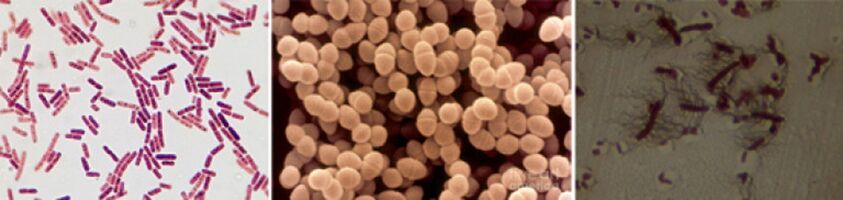

Les agents pathogènes responsables de la prostatite chronique comprennent les agents pathogènes suivants :

- Dans 90 % des cas, la maladie implique des bactéries à Gram négatif telles que Escherichia coli (Escherichia coli), Enterococcus faecalis (entérocoques fécaux) et, un peu moins fréquemment, Pseudomonas aeruginosa, Klebsiella spp., Proteus spp., Pseudomonas aeruginosa, Enterobacter aerogenes et Acinetobacter a détecté spp. Les bactéries à Gram positif telles que les entérocoques, les streptocoques et les staphylocoques sont rares.

- Le rôle des staphylocoques à coagulase négative, des ureaplasma, des chlamydia, des Trichomonas, des Gardnerella, des bactéries anaérobies et des champignons du genre Candida n'est pas entièrement compris.